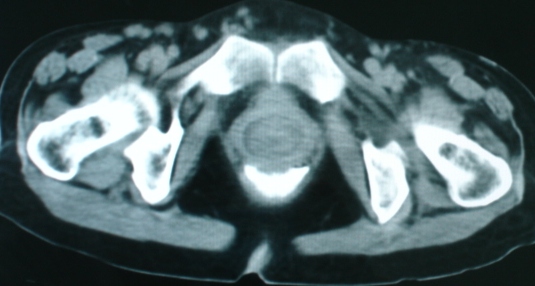

以下是引用zsl6918在2008-11-4 19:14:00的发言:[br]多发转移性改变,子宫改变不除外为原发灶